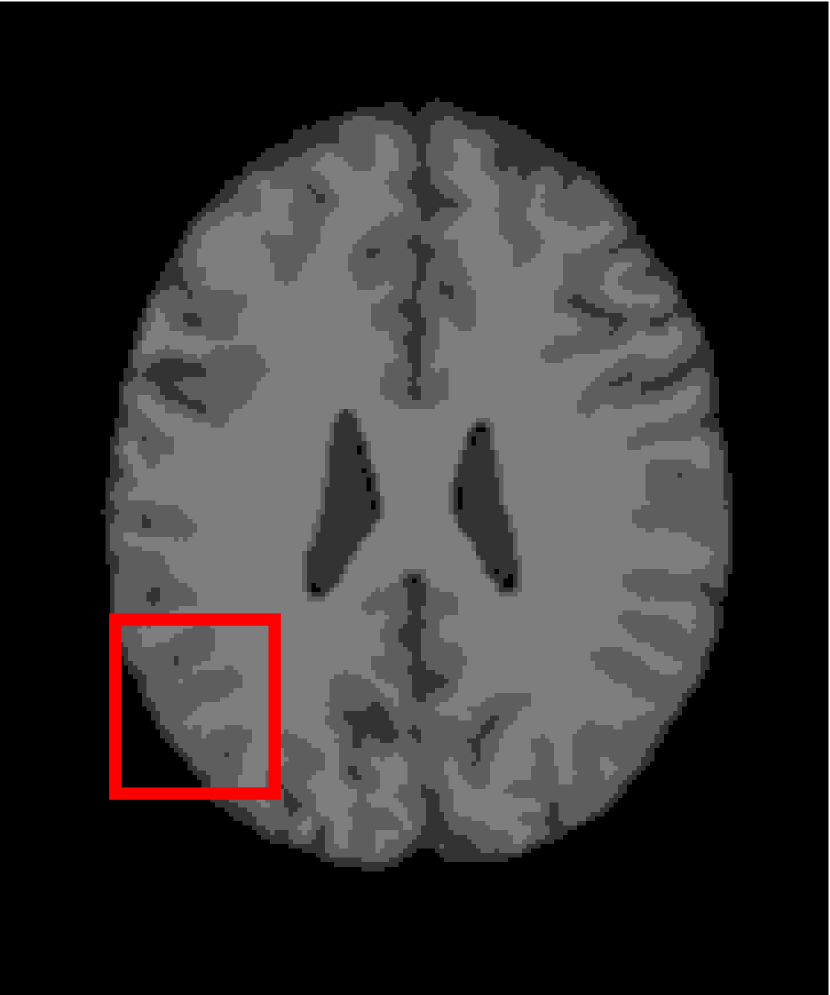

Next, we representatively segment five medical images from BrianWeb. They are represented as five slices in the axial plane with a sequence of 70, 80, 90, 100 and 110, which are generated by T1 modality with slice thickness of 1mm resolution, 9% noise and 20% intensity non-uniformity. Here, we set c=4𝑐4c=4 for all cases. The comparison between WRFCM and its peers are shown in Fig. 9 and Table II. The best values are in bold.

Figure 9: Segmentation results on five medical images. The parameter: ϕ=5.35italic-ϕ5.35\phi=5.35. From top to bottom: noisy images, ground truth, and results of FCM_S1, FCM_S2, FLICM, KWFLICM, FRFCM, WFCM, DSFCM_N, and WRFCM.

By a view of the marked red square in Fig. 9, we find that FCM_S1, FCM_S2, FLICM, KWFLICM and DSFCM_N are vulnerable to noise and intensity non-uniformity. They give rise to the change of topological shapes to some extent. Unlike them, FRFCM and WFCM achieve sufficient noise removal. However, they produce overly smooth contours. Compared with its seven peers, WRFCM can not only suppress noise adequately but also acquire accurate contours. Moreover, it yields the visual result closer to ground truth than its peers. As Table II shows, WRFCM obtains optimal SA, SDS and MCC results for all five medical images. As a conclusion, it outperforms its peers visually and quantitatively.